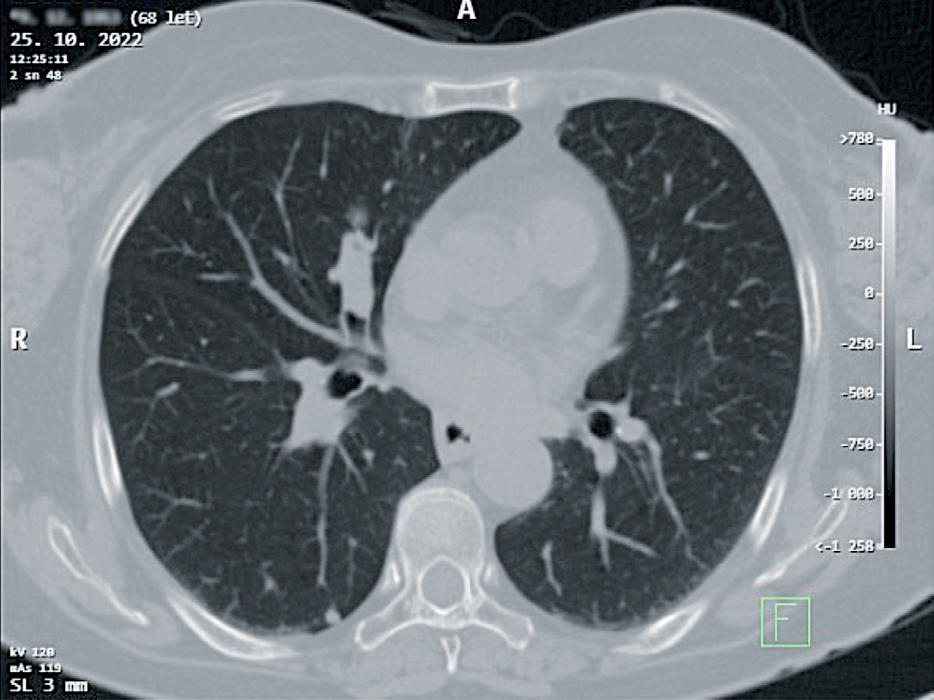

obr. 3.3 Nádory anatomicky vhodné pro videotorakoskopické nebo videorobotické operační řešení; a) potvrzený 2,5cm nemalobuněčný plicní karci nom v S3 levé plíce u 73letého muže, b) endobronchiální karcinoid středního lobárního bronchu u 68leté ženy

Pokud musíme uvažovat o minitorakotomii, jsou pro videotorakoskopickou plicní resekci ideální nádory o velikosti do 5 cm (obr. 3.3). Tedy malignity o klasi fikaci do T2b tumoru dle 8. vydání TNM klasifikace v české verzi z roku 2018 [33] . Minitorakotomií lze odstranit i nádory a nenádorové infiltrace větší, než je rozměr kožního řezu minitorakotomie [34]. Stlačitelnost a elasticita tkáně postižené nádorem je velmi malá. Prů chodnost nádoru minitorakotomií se odvíjí od rozměrů nejmenšího příčného průřezu afekce. Nejmenší příčný průměr kombinace nádoru s případným zánětlivým in filtrátem v okolí by neměl přesahovat rozměry minito rakotomie.

obr. 3.5 Příklady nádorů, které jsou k videotorakoskopickému operování z anatomického hlediska sice méně vhodné, ale videotorakoskopická operace by měla být proveditelná; a) nemalobuněčný plicní karcinom o větším průměru než 6,5 cm s centrální kavernou, abscesem, u 58letého muže, navíc s těsným vztahem k hrudní stěně, b) endobronchiální karcinom s přetrvávající objemnou postobstrukční infiltrací S3 u 47letého muže. Pohled na indikaci videotorakoskopického přístupu je relativní. Ovlivňuje jej technické vybavení, zkušenost i naturel operujícího. Pokud pomineme velikost nádoru nad 6 cm (a), a tím možnou potřebu větší minitorakotomie, pak videorobotický přístup by zde mohl být naopak výhodou při oddělování nádoru od hrudní stěny nebo dokonce při její resekci